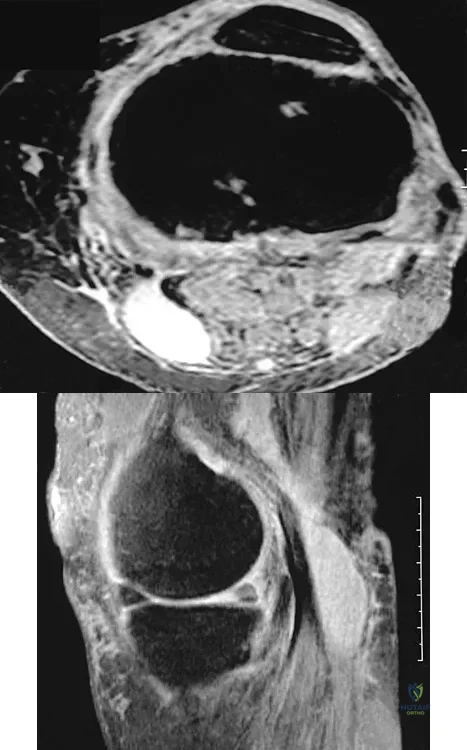

An 80-year-old woman notes a painless mass posterior to her left knee. MRI scans are shown in Figures 31a and 31b. What is the best course of action?

Explanation